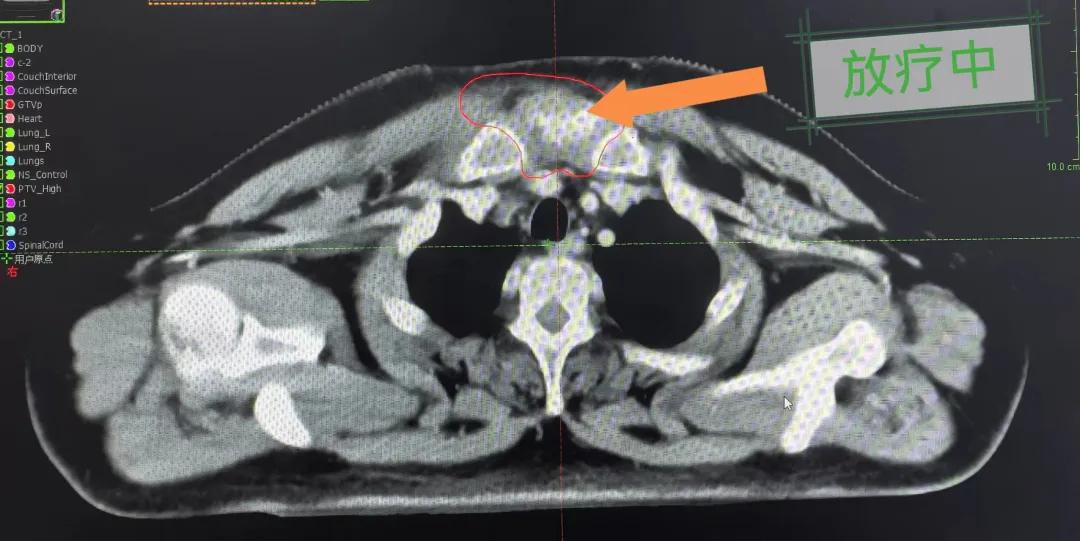

隨后,趙亮主任帶領(lǐng)放療團(tuán)隊(duì)以最快的速度完成了患者的放射治療計(jì)劃,在保證放療精準(zhǔn)打擊腫瘤的同時(shí),利用先進(jìn)的三維立體精確放療技術(shù),最大限度的避免心臟、肺部的損傷發(fā)生,整體治療精準(zhǔn)度達(dá)到1mm以內(nèi)。經(jīng)過(guò)10次的放射治療后,患者疼痛已明顯減輕,胸部腫物肉眼可見的縮小,患者及家屬臉上終于露出久違的笑臉。

治療期間,患者沒有出現(xiàn)明顯不適,治療結(jié)束后,患者胸壁腫物由最初8cm縮小至約1cm,后患者至外科行手術(shù)治療。